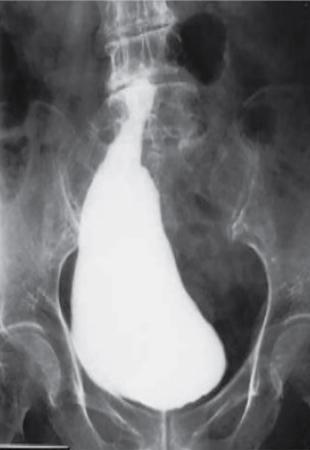

• Filled view of bladder and VUJ – preferably bilateral oblique views of a full bladder to visualize the VUJs. This can be done by positioning the bladder at the inferior most part of screen and tilting the tube along the course of the ureter. Abnormalities of the bladder like congenital or acquired bladder diverticula, patent urachus can be diagnosed on this image (Figs. 10.6.7 and 10.6.8). Conditions like pelvic lipomatosis can also be diagnosed by appreciating the ‘pear shaped’ bladder. An anteroposterior imaging of the renal fossa can be done prior to voiding in case reflux is detected in the late bladder filling phase. To follow the principle of ALARA and Image Gently, while imaging female patients, spot radiographs of the renal fossa should be centred on the fossa not including the region of the gonads or the urine-filled bladder.

• Voiding urethra view

• Male patient – steep oblique position is optimum (Fig. 10.6.9).

• Female patient – anteroposterior view is preferred which will show a classical spinning top appearance (Fig. 10.6.10).

• This image will depict abnormalities of the posterior urethra like posterior urethral valve, outlet obstruction as well as point towards a possible VUR (Fig. 10.6.11). One image can be obtained with the catheter in situ and another with the catheter removed. Voiding with catheter in situ allows refilling if needed and drain bladder in patients who are unable to void completely. A neurologic abnormality, bladder spasm or active bladder infection can be indicated by low voiding volumes. However, reproducibility of these findings should be documented for this observation to be reliable. An unexpectedly large bladder capacity may be seen in sensitive voiders, dysfunctional voiding or noncompliant recently trained children. May be due to noncompliance in recently toilet-trained children.